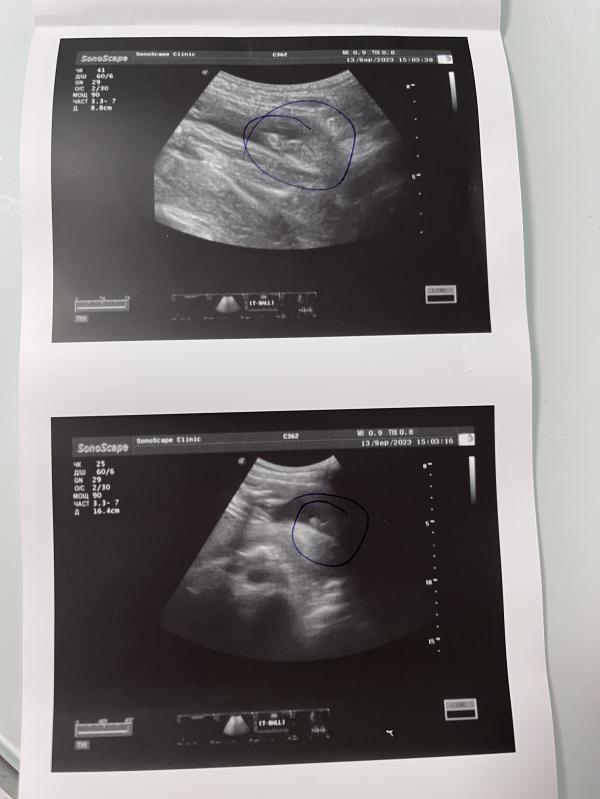

Сегодня ходила на узи для подтверждение пола. Первый раз пошла в 17 недель и в 25 решила перед покупкой вещей так сказать убедиться. Врач даже обвела подтверждение, что мальчик 😄

Хотела сделать красивое фото на память, но сын походу весь в отца и уже второй раз отказывается позировать